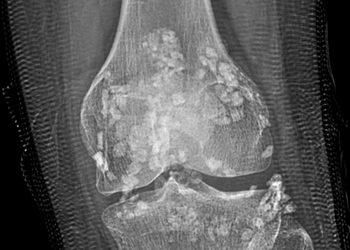

"Di sản các nhà khoa học Việt Nam và thế giới - Heritage of Vietnamese and world scientists" do tổ ...

Kiem Ha Hoang